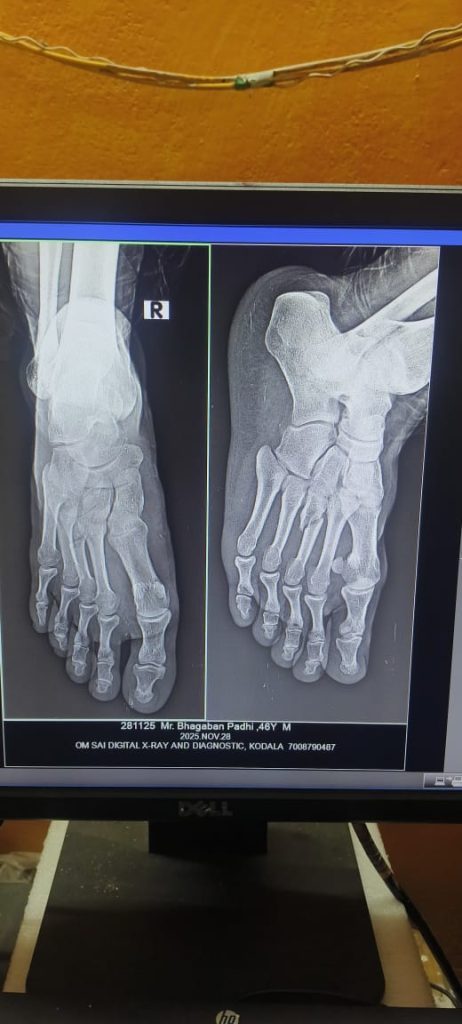

ଏବେ କାଉସିଲର ଙ୍କ ପାଇଁ ଅସୁରକ୍ଷିତ ପାଲଟିଲା କୋଦଳା ଏନଏସି…. ଯାହା କୁହାଯାଉଛି ଅଧକ୍ଷ ଙ୍କ ନିର୍ଦେଶ ରେ ଭଡାଟିଆ ଗୁଣ୍ଡା ଙ୍କ ଦ୍ୱାରା ଏନଏସି ପରିସରରେ ବର୍ବୋରୋଚିତ ଆକ୍ରମଣ କରାଯାଇଥିବା ଅଭିଯୋଗ ରୁ ଜଣାଯାଇଛି.. ଯାହା ସୂଚନା ମିଳିଛି, କୋଦଳା NAC ରେ ଗତକାଲି 11 ଟି କାମର ଅନିୟମିତତା ଆଶଙ୍କା କରି ହୋଇଥିବା ଟେଣ୍ଡର ତଥ୍ୟ ମାଗିବାରୁ ବରିଷ୍ଠ ସାମ୍ବାଦିକ ତଥା ଏନଏସି ର 11 ନମ୍ବର ୱାର୍ଡ ର କାଉସିଲର ଭଗବାନ ପାଢ଼ୀ ଙ୍କୁ ମରଣାନ୍ତକ ଆକ୍ରମଣ ହୋଇଛି l ଆକ୍ରମଣ ରେ ଭଗବାନ ପାଢ଼ୀ ଙ୍କ ଗୋଡ଼ ଭାଙ୍ଗି ଯାଇଥିବା ବେଳେ ସଂଘବଧ ଭାବେ ଆକ୍ରମଣ କରି ତାଙ୍କ ସାର୍ଟ ଚିରି ସୁନା ଚେନ ଝିକି ନେଇଯାଇଥିବା ଅଭିଯୋଗ ହୋଇଛି…

ସୂଚନା ଅନୁସାରେ ସରକାର ଙ୍କ ପକ୍ଷରୁ ଗୁରୁବାର ଦିନ କୋଦଳା ଏନଏସି ର 11 ଗୋଟି ଉନ୍ନୟନ କାର୍ଯ୍ୟକୁ ନେଇ ଟେଣ୍ଡର ଅନୁଷ୍ଠିତ ହେବାପାଇଁ ସମୟ ଧାର୍ଯ୍ୟ ହୋଇଥିଲା l ତେବେ ଏହି ଟେଣ୍ଡର ପ୍ରକ୍ରିୟା ଅଧକ୍ଷ ଏବଂ କାର୍ଯ୍ୟନିର୍ବାହୀ ଅଧିକାରୀ ଙ୍କ ପ୍ରତ୍ୟକ୍ଷ ତତ୍ୱାବଧାନ ରେ ବହୁ ଅନିୟମିତତା ହୋଇଥିବା ଦେଖି 11 ନମ୍ବର କାଉସିଲର ଏହାକୁ ବିରୋଧ କରିଥିଲେ l ଟେଣ୍ଡର ପ୍ରକ୍ରିୟା ର ସମସ୍ତ ତଥ୍ୟ ସହ ସିସିଟିଭି ପୁଟେଜ ଆରଟିଆଇ ଜରିଆରେ ଅଧିକାରୀ ଙ୍କୁ ମାଗିଥିବା ଯୋଗୁଁ ଅଧ୍ୟକ୍ଷ ନିଜେ ପ୍ରତିକ୍ରିୟଶୀଳ ହୋଇ ଅପରାହ୍ନ 3 ଟା ସମୟରେ କାର୍ଯ୍ୟାଳୟ ପରିସରରେ ଭଗବାନ ପାଢ଼ୀ ଠିଆ ହୋଇଥିବା ସମୟରେ ଅଧକ୍ଷ ଙ୍କ ନିର୍ଦେଶ ରେ ପାଞ୍ଚରୁ ଉର୍ଦ୍ଧ ଗୁଣ୍ଡା ଶ୍ରେଣୀ ର ଲୋକ ଆସି ତାଙ୍କ ସହ ଯୁକ୍ତି ତର୍କ କରିବା ସହିତ ବିଭିନ୍ନ ମାରଣାସ୍ତ୍ର ରେ ଆକ୍ରମଣ କରିଥିଲେ l ଆକ୍ରମଣ ରେ ଭଗବାନ ପାଢ଼ୀ ଙ୍କ ଗୋଡ଼ ଭାଙ୍ଗିବା ସହ ଛାତି, ହାତ ଓ ମୁଣ୍ଡ ରେ ଗଭୀର ଆଘାତ ଲାଗିବା ସହିତ ସୁନା ଚେନ କୁ ଛଡାଇ ନେଇ ଚାଲିଯାଇଥିଲେ l ଆକ୍ରମଣ ପରେ ଗୁରୁତର ଭଗବାନ ଙ୍କୁ କୋଦଳା ଗୋଷ୍ଠୀ ସ୍ୱାସ୍ଥ୍ୟକେନ୍ଦ୍ର ରେ ଭର୍ତି କରିଥିବା ବେଳେ ଏଠାରେ ପ୍ରାଥମିକ ଚିକିତ୍ସା ପରେ ବ୍ରହ୍ମପୁର ସ୍ଥିତ ଏମକେସିଜି ମିଡିକାଲ କୁ ସ୍ଥାନାନ୍ତର କରାଯାଇଛି l ତେବେ ଏଠି ବଡ଼ ପ୍ରଶ୍ନ ଜଣେ କାଉସିଲର କୁ ଏନଏସି ପରିସରରେ ଆକ୍ରମଣ ପରେ କାହିଁକି ଅଧିକାରୀ ନୀରବ କାହିଁକି ? ଯଦି ଏନଏସି ପରିସର କାଉସିଲର ଙ୍କ ପାଇଁ ଅସୁରକ୍ଷିତ ତେବେ ଅଞ୍ଚଳବାସୀ କେତେ ସୁରକ୍ଷିତ? ତାହାକୁ ନେଇ ପ୍ରଶ୍ନ ଉଠିଲାଣି… ଆଧ୍ୟକ୍ଷ ଙ୍କ ଦୁର୍ନତି ର ତଦନ୍ତ କରିବା ସହ ଘଟଣା ଉପରେ ଦୃଷ୍ଟି ଦେଇ ଅପରାଧୀ ମାନଙ୍କୁ ଗିରଫ ନକଲେ ଆଗକୁ ସ୍ଥିତି ବିଗିଡ଼ିବା ସହ ସମ୍ଭାବ୍ୟ ଆଇନ ଶୃଙ୍ଖଳା ପରିସ୍ଥିତି କୁ ନେଇ କୋଦଳା ଅଞ୍ଚଳରେ ଆଲୋଚନା ଚାଲିଛି..